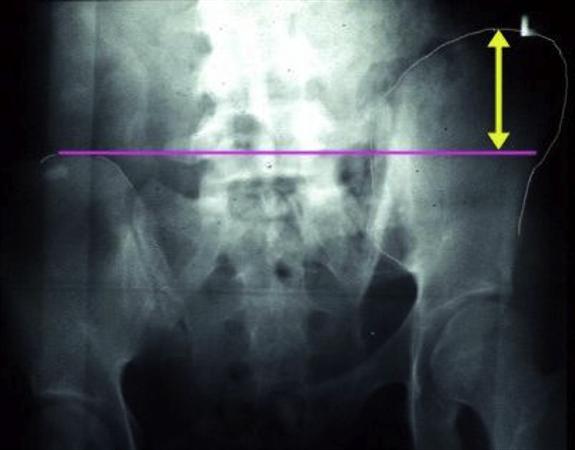

VS (vertical shear)는 hemipelvis 형태로 전이가 이뤄집니다. symphysis가 벌어지기도 하고 rami, iliac wing, sacral fx, SI jt posteriorly 모두 손상을 입게 됩니다.